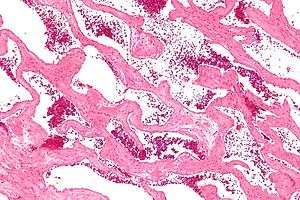

Usually the first step a doctor uses is an X-ray computed tomography (CT) scan to identify cavernous hemangioma. Magnetic resonance imaging (MRI) can be used to identify cavernous hemangioma. The phrase “bag of worms” is usually used to describe the appearance of hemangiomas in such images.[15] Angiography can be used by using a dye that is injected into the blood stream allowing for the contrast of hemangioma to show up. Additionally, doctors can use a biopsy by obtaining a sample of tissue of the tumor using a needle to examine it under a microscope. It is essential to diagnose cavernous hemangioma because treatments for this benign tumor are less aggressive than that of cancerous tumors, such as angiosarcoma. In some cases, it is possible for a surgery to be used as a method of diagnosis if imaging is not enough. The lesion is viewed under the microscope to diagnose cavernoma.[16]